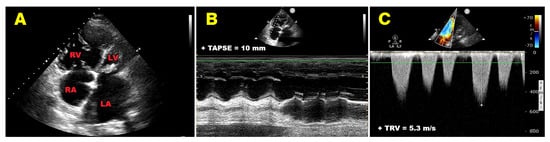

New in @ESC_Journals #EHJDigitalHealth: A cardiovascular biological age from focused cardiac #POCUS identifies accelerated agers and is strongly linked to adverse metabolic profiles (including >2× odds of metabolic syndrome). Read the full paper: https://t.co/YArQGNev58 pic.twitter.com/1l7i1VhIbx

— Elad Maor (@maor_elad) March 19, 2026